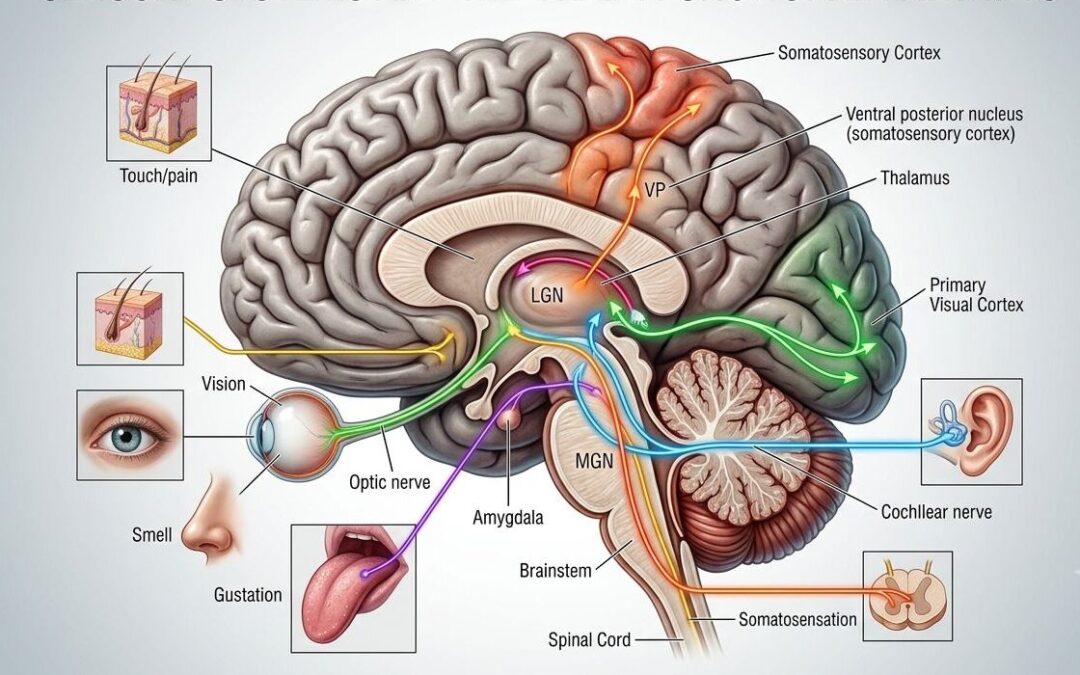

But physiology is not only about state—it’s also about timing.

Circadian rhythms regulate a wide range of biological processes, including hormone secretion, immune function, metabolism, and gene expression.6 When these rhythms are aligned, they support physiological stability. When they are disrupted, the effects extend far beyond fatigue.

The Nervous System, Inflammation, and the Microbiome

The autonomic nervous system adds another layer of complexity.

The balance between sympathetic (“fight or flight”) and parasympathetic (“rest and digest”) activity regulates processes ranging from inflammation to digestion to immune function.¹² Chronic sympathetic activation has been associated with: